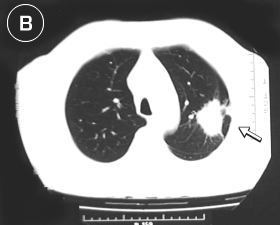

Corte Tomográfico "B"

en tercio superior del tórax:

• Corte a nivel de la lesión: Lesión pulmonar, redondeada, sólida y de bordes irregulares, espiculados, de tamaño aproximado 3 x 4 cm. adosada aparentemente a la pared torácica posterior.